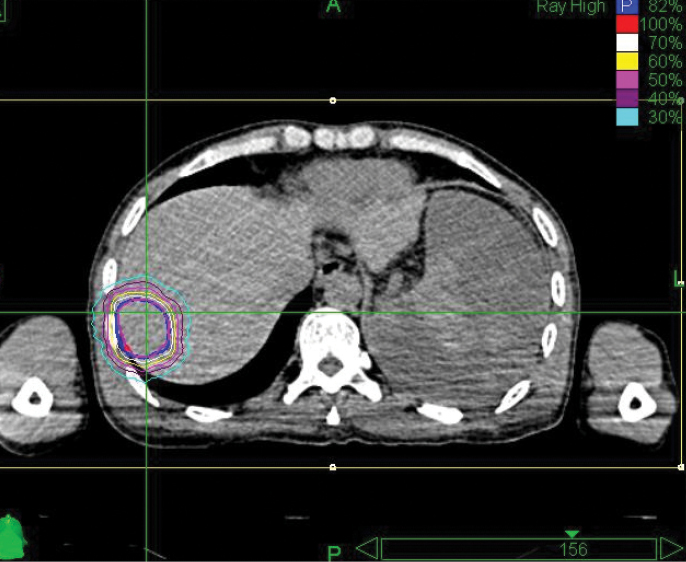

A 42-year-old male with chronic hepatitis B was initially diagnosed with primary liver cancer. He received radiofrequency ablation. Then an MRI revealed recurrence in front of the original lesion. The patient underwent interventional therapy in March 2012, but was hospitalized a month later when a CT showed a residual tumor and acute cholecystitis. Diagnosis was hepatocellular carcinoma, T2N0M0, Stage II. The patient was treated with the CyberKnife® System at 302 Hospital of PLA.

The initial follow-up took place four months after treatment, and CT showed no residual tumor. At the eight-month follow-up, MRI examination showed a region of necrosis in the location of the right lobe tumor. At 32 months post treatment an MRI showed no residual disease or any late toxicities.

“The CyberKnife System’s ability to track and adjust the beam with fiducials is key to giving high-dose SBRT to the liver.”

– Li Yu, M.D., Chairman, Radiation Oncology, 302 Hospital of PLA